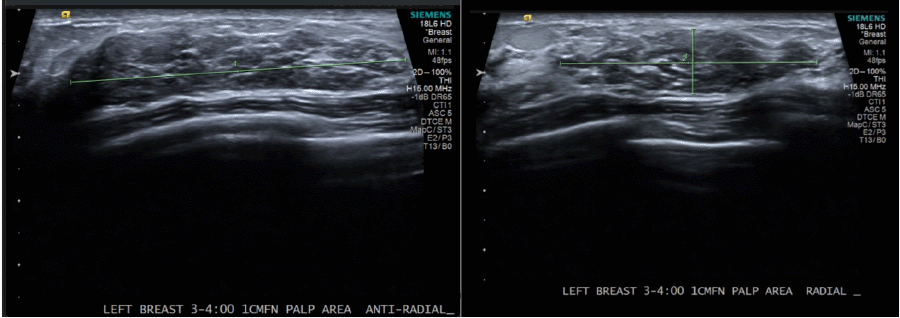

A 32-year-old female with a family history of a paternal grandmother diagnosed with breast cancer at age 65, followed by colon cancer at age 80, reported a palpable left breast mass for almost a year. Diagnostic imaging revealed a 5.2 × 1.1 × 4.3 cm heterogeneous hypoechoic mass at the left 3-to-4 o'clock position, which was suspicious for malignancy (Figure 1 and Figure 2). Subsequent bilateral breast MRI revealed a left breast 7.2 × 2.0 × 4.4 cm avid non-mass enhancement with a wedge-shaped distribution abutting the chest wall, highly suggestive of malignancy and mildly prominent left axillary lymph nodes (Figure 3).

Figure 2. Diagnostic Ultrasound of Left Breast. Published with Permission